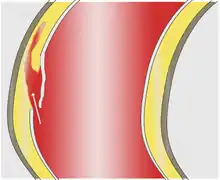

As with all other arteries, the aorta is made up of three layers, the intima, the media, and the adventitia. The intima is in direct contact with the blood inside the vessel, and mainly consists of a layer of endothelial cells on a basement membrane; the media contains connective and muscle tissue, and the vessel is protected on the outside by the adventitia, comprising connective tissue.[25]

In an aortic dissection, blood penetrates the intima and enters the media layer. The high pressure rips the tissue of the media apart along the laminated plane splitting the inner two-thirds and the outer one-third of the media apart.[26] This can propagate along the length of the aorta for a variable distance forward or backward. Dissections that propagate towards the iliac bifurcation (with the flow of blood) are called anterograde dissections and those that propagate towards the aortic root (opposite of the flow of blood) are called retrograde dissections. The initial tear is usually within 100 mm of the aortic valve, so a retrograde dissection can easily compromise the pericardium leading to a hemopericardium. Anterograde dissections may propagate all the way to the iliac bifurcation of the aorta, rupture the aortic wall, or recanalize into the intravascular lumen leading to a double-barrel aorta. The double-barrel aorta relieves the pressure of blood flow and reduces the risk of rupture. Rupture leads to hemorrhaging into a body cavity, and prognosis depends on the area of rupture. Retroperitoneal and pericardial ruptures are both possible.[27]

The initiating event in aortic dissection is a tear in the intimal lining of the aorta. Due to the high pressures in the aorta, blood enters the media at the point of the tear. The force of the blood entering the media causes the tear to extend. It may extend proximally (closer to the heart) or distally (away from the heart) or both. The blood travels through the media, creating a false lumen (the true lumen is the normal conduit of blood in the aorta). Separating the false lumen from the true lumen is a layer of intimal tissue known as the intimal flap.

The vast majority of aortic dissections originate with an intimal tear in either the ascending aorta (65%), the aortic arch (10%), or just distal to the ligamentum arteriosum in the descending thoracic aorta (20%).

As blood flows down the false lumen, it may cause secondary tears in the intima. Through these secondary tears, the blood can re-enter the true lumen.